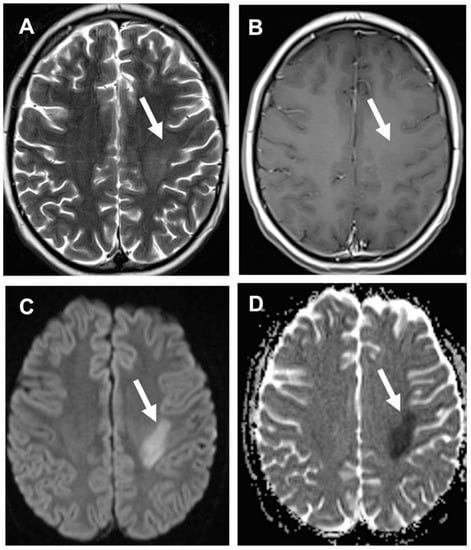

3.3. Stroke-like Migraine Attacks after Radiation Therapy

- Kerklaan, J.P.; Lycklama á Nijeholt, G.J.; Wiggenraad, R.G.J.; Berghuis, B.; Postma, T.J.; Taphoorn, M.J.B. SMART syndrome: A late reversible complication after radiation therapy for brain tumours. J. Neurol. 2011, 258, 1098–1104. [Google Scholar] [CrossRef] [PubMed] [Green Version]

- Rigamonti, A.; Lauria, G.; Mantero, V.; Filizzolo, M.; Salmaggi, A. SMART (stroke-like migraine attack after radiation therapy) syndrome: A case report with review of the literature. Neurol. Sci. 2016, 37, 157–161. [Google Scholar] [CrossRef]

- Armstrong, A.E.; Gillan, E.; Di Mario, F.J. SMART Syndrome (Stroke-Like Migraine Attacks After Radiation Therapy) in Adult and Pediatric Patients. J. Child Neurol. 2014, 29, 336–341. [Google Scholar] [CrossRef]

- Farid, K.; Meissner, W.G.; Samier-Foubert, A.; Barret, O.; Menegon, P.; Rouanet, F.; Fernandez, P.; Orgogozo, J.M.; Allard, M.; Tison, F.; et al. Normal Cerebrovascular Reactivity in Stroke-Like Migraine Attacks After Radiation Therapy Syndrome. Clin. Nucl. Med. 2010, 35, 583–585. [Google Scholar] [CrossRef]

- Black, D.F.; Morris, J.M.; Lindell, E.P.; Krecke, K.N.; Worrell, G.A.; Bartleson, J.D.; Lachance, D.H. Stroke-Like Migraine Attacks after Radiation Therapy (SMART) Syndrome Is Not Always Completely Reversible: A Case Series. Am. J. Neuroradiol. 2013, 34, 2298–2303. [Google Scholar] [CrossRef] [Green Version]